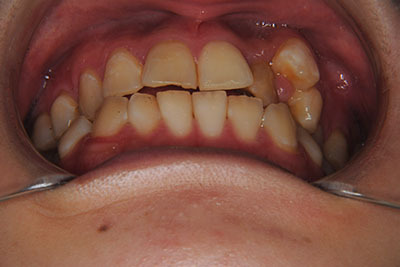

①主訴:左上八重歯を治したい。

②診断名:AngleⅠ級叢生

お口の中を診ますと、左上第二小臼歯が歯列の内側に生え、左上犬歯のスペースは全くない八重歯となっていました。検査結果から骨格的な不正はなく。上奥歯が前にずれたかみ合わせで前歯は合っていて出っ歯ではないので左右1本ずつ歯列からはみ出した状態であることがわかりました。上の奥歯を横の歯1本分後ろにずらすことは困難なので、右上中側に生えている第二小臼歯と八重歯である左上犬歯の次の歯=第一小臼歯の2本を抜歯し治療しました。